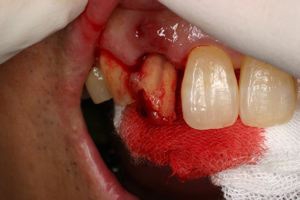

主訴-前歯が腫れて痛い。治療法のうち、ブリッジとインプラントを説明して隣の前歯を削らないですむことからインプラントを選択された。

抜歯を行う。折れていた位置がかなり深い位置であるのがわかる。

歯根も抜歯